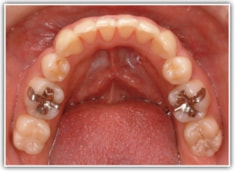

上顎前突ケース

治療法:表の矯正(T21ブラケット)

治療前